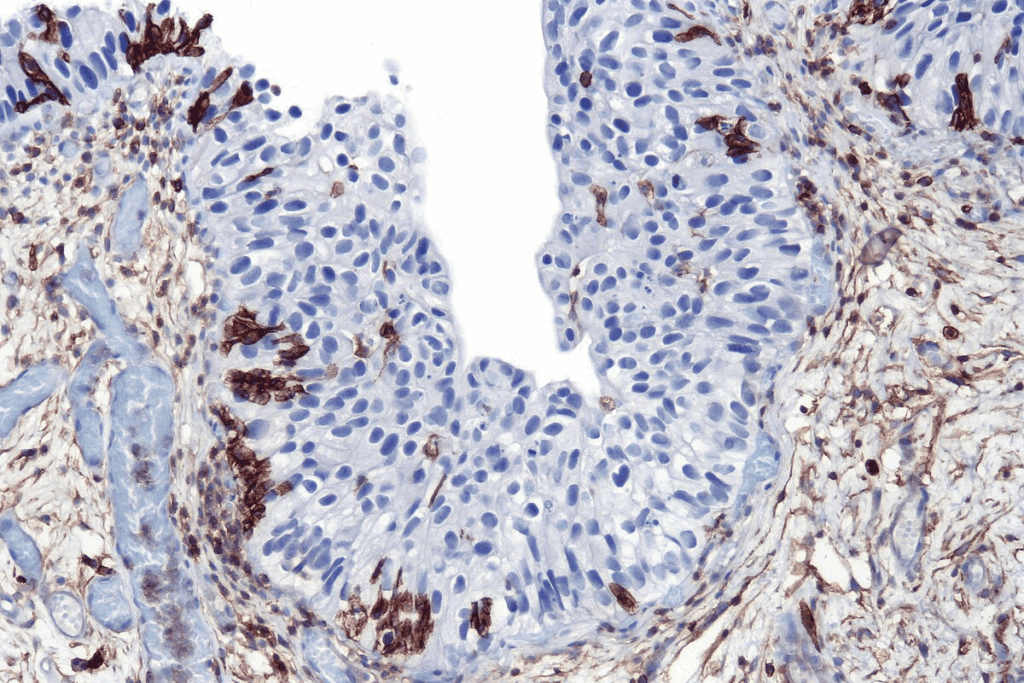

Carcinoma in situ has cancer cells that haven’t crossed the basement membrane. This membrane is a key barrier between cells and tissue. These cells look different from normal cells under a microscope.

Doctors diagnose carcinoma in situ by looking at these cell changes during a biopsy. These changes can range from mild to severe, showing how abnormal the cells are.

Looking at tissues under a microscope is the best way to diagnose CIS. It confirms CIS and tells it apart from invasive cancer.

It checks the cells and how they are arranged. Histological grading and molecular markers give more info on how likely the cancer is to grow.